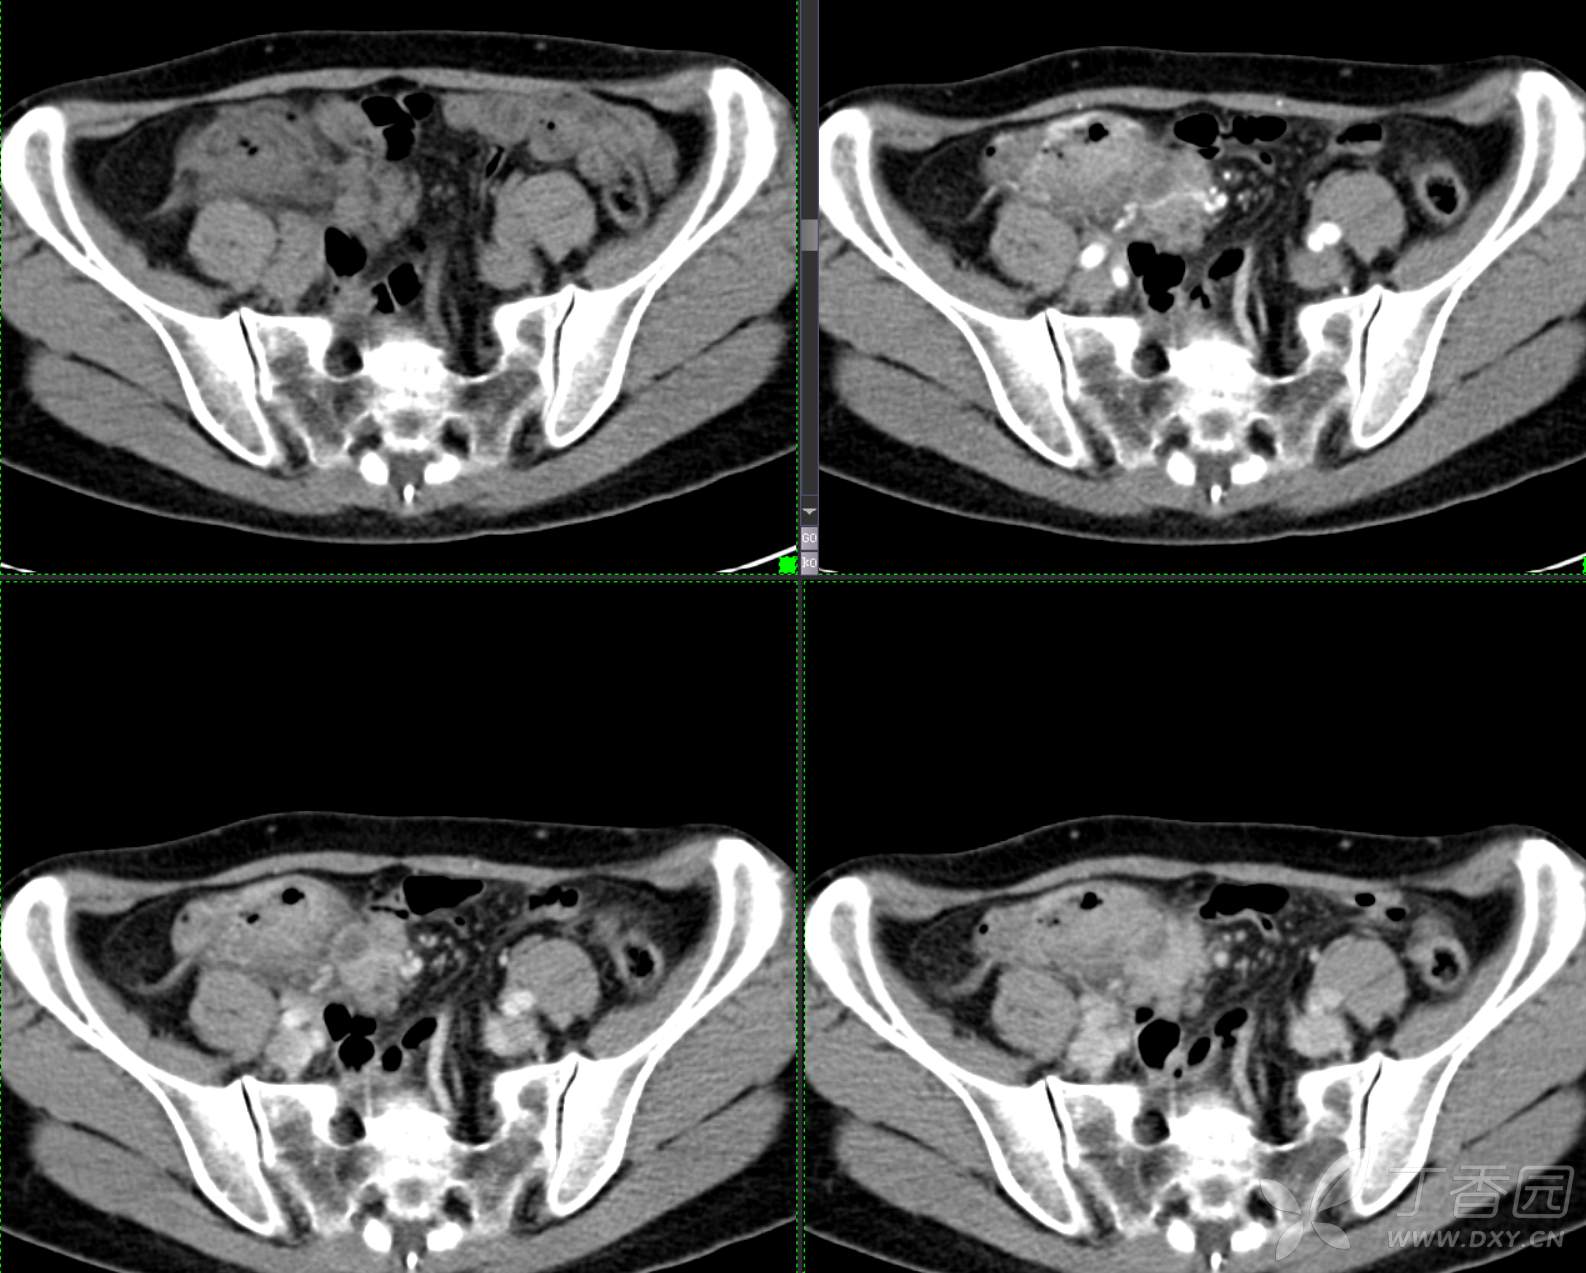

腹组13:患者,女,62岁,大便习惯改变2月余

主 诉: 【大便性状改变2月余】

现病史: 患者2月余前无明显诱因下出现大便次数增多,无明显血便黑便及粘液脓血便,大便次数由1次/日增加至2-3次/日,大便形状变细如小指,偶稀软不成形,无腹痛腹胀腹泻,无恶心呕吐、胸闷气促,肛门排气通畅,无发热盗汗。至当地医院就诊,行肠镜检查发现"回盲部占位"。为进一步治疗,我院门诊拟"回盲部肿瘤"收住入院。